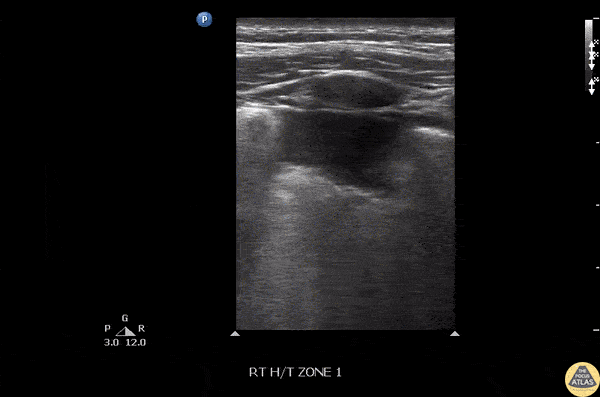

Pulmonary - Pneumonia-Subpleural Consolidation

Irregular pleural lining, B lines, and subpleural consolidation best seen with a linear probe. Image courtesy of Robert Jones DO, FACEP @RJonesSonoEM Director, Emergency Ultrasound; MetroHealth Medical Center; Professor, Case Western Reserve Medical School, Cleveland, OH View his original post here